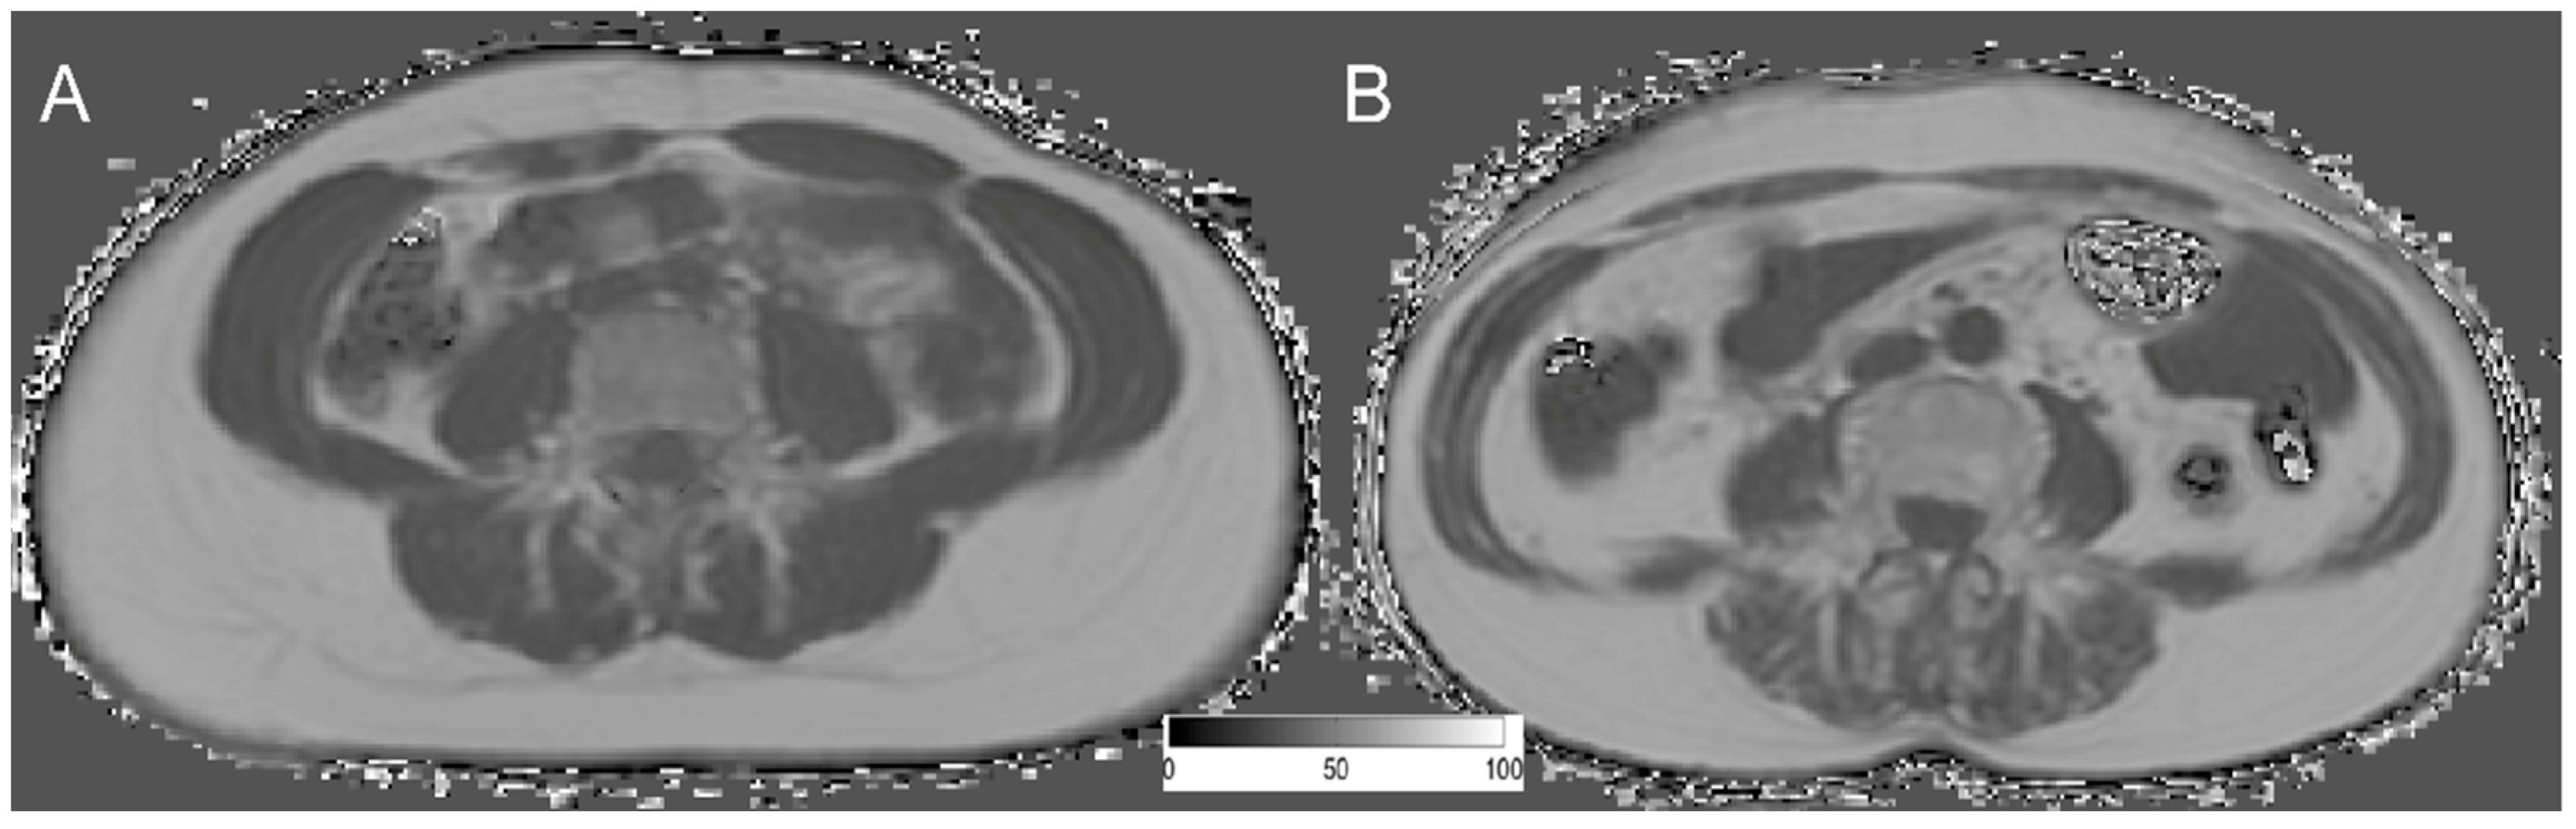

2.2. MR Imaging (T2 mDixon Quant)

2.3. PDFF Mapping